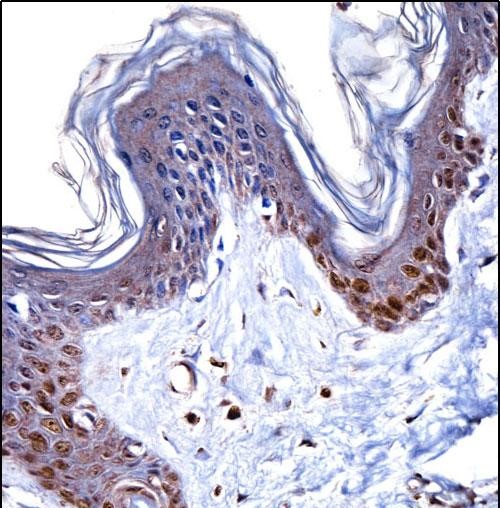

| IHC | 1/100-1/500 | Human,Mouse,Rat |

This antibody is commonly used in research to detect HMGN1 expression and localization in various biological samples via techniques like Western blotting, immunofluorescence, or immunohistochemistry. It helps investigate HMGN1's involvement in cellular processes such as DNA damage response, differentiation, and cancer progression. Studies have linked HMGN1 dysregulation to diseases, including certain cancers, due to its impact on oncogene or tumor suppressor activity.